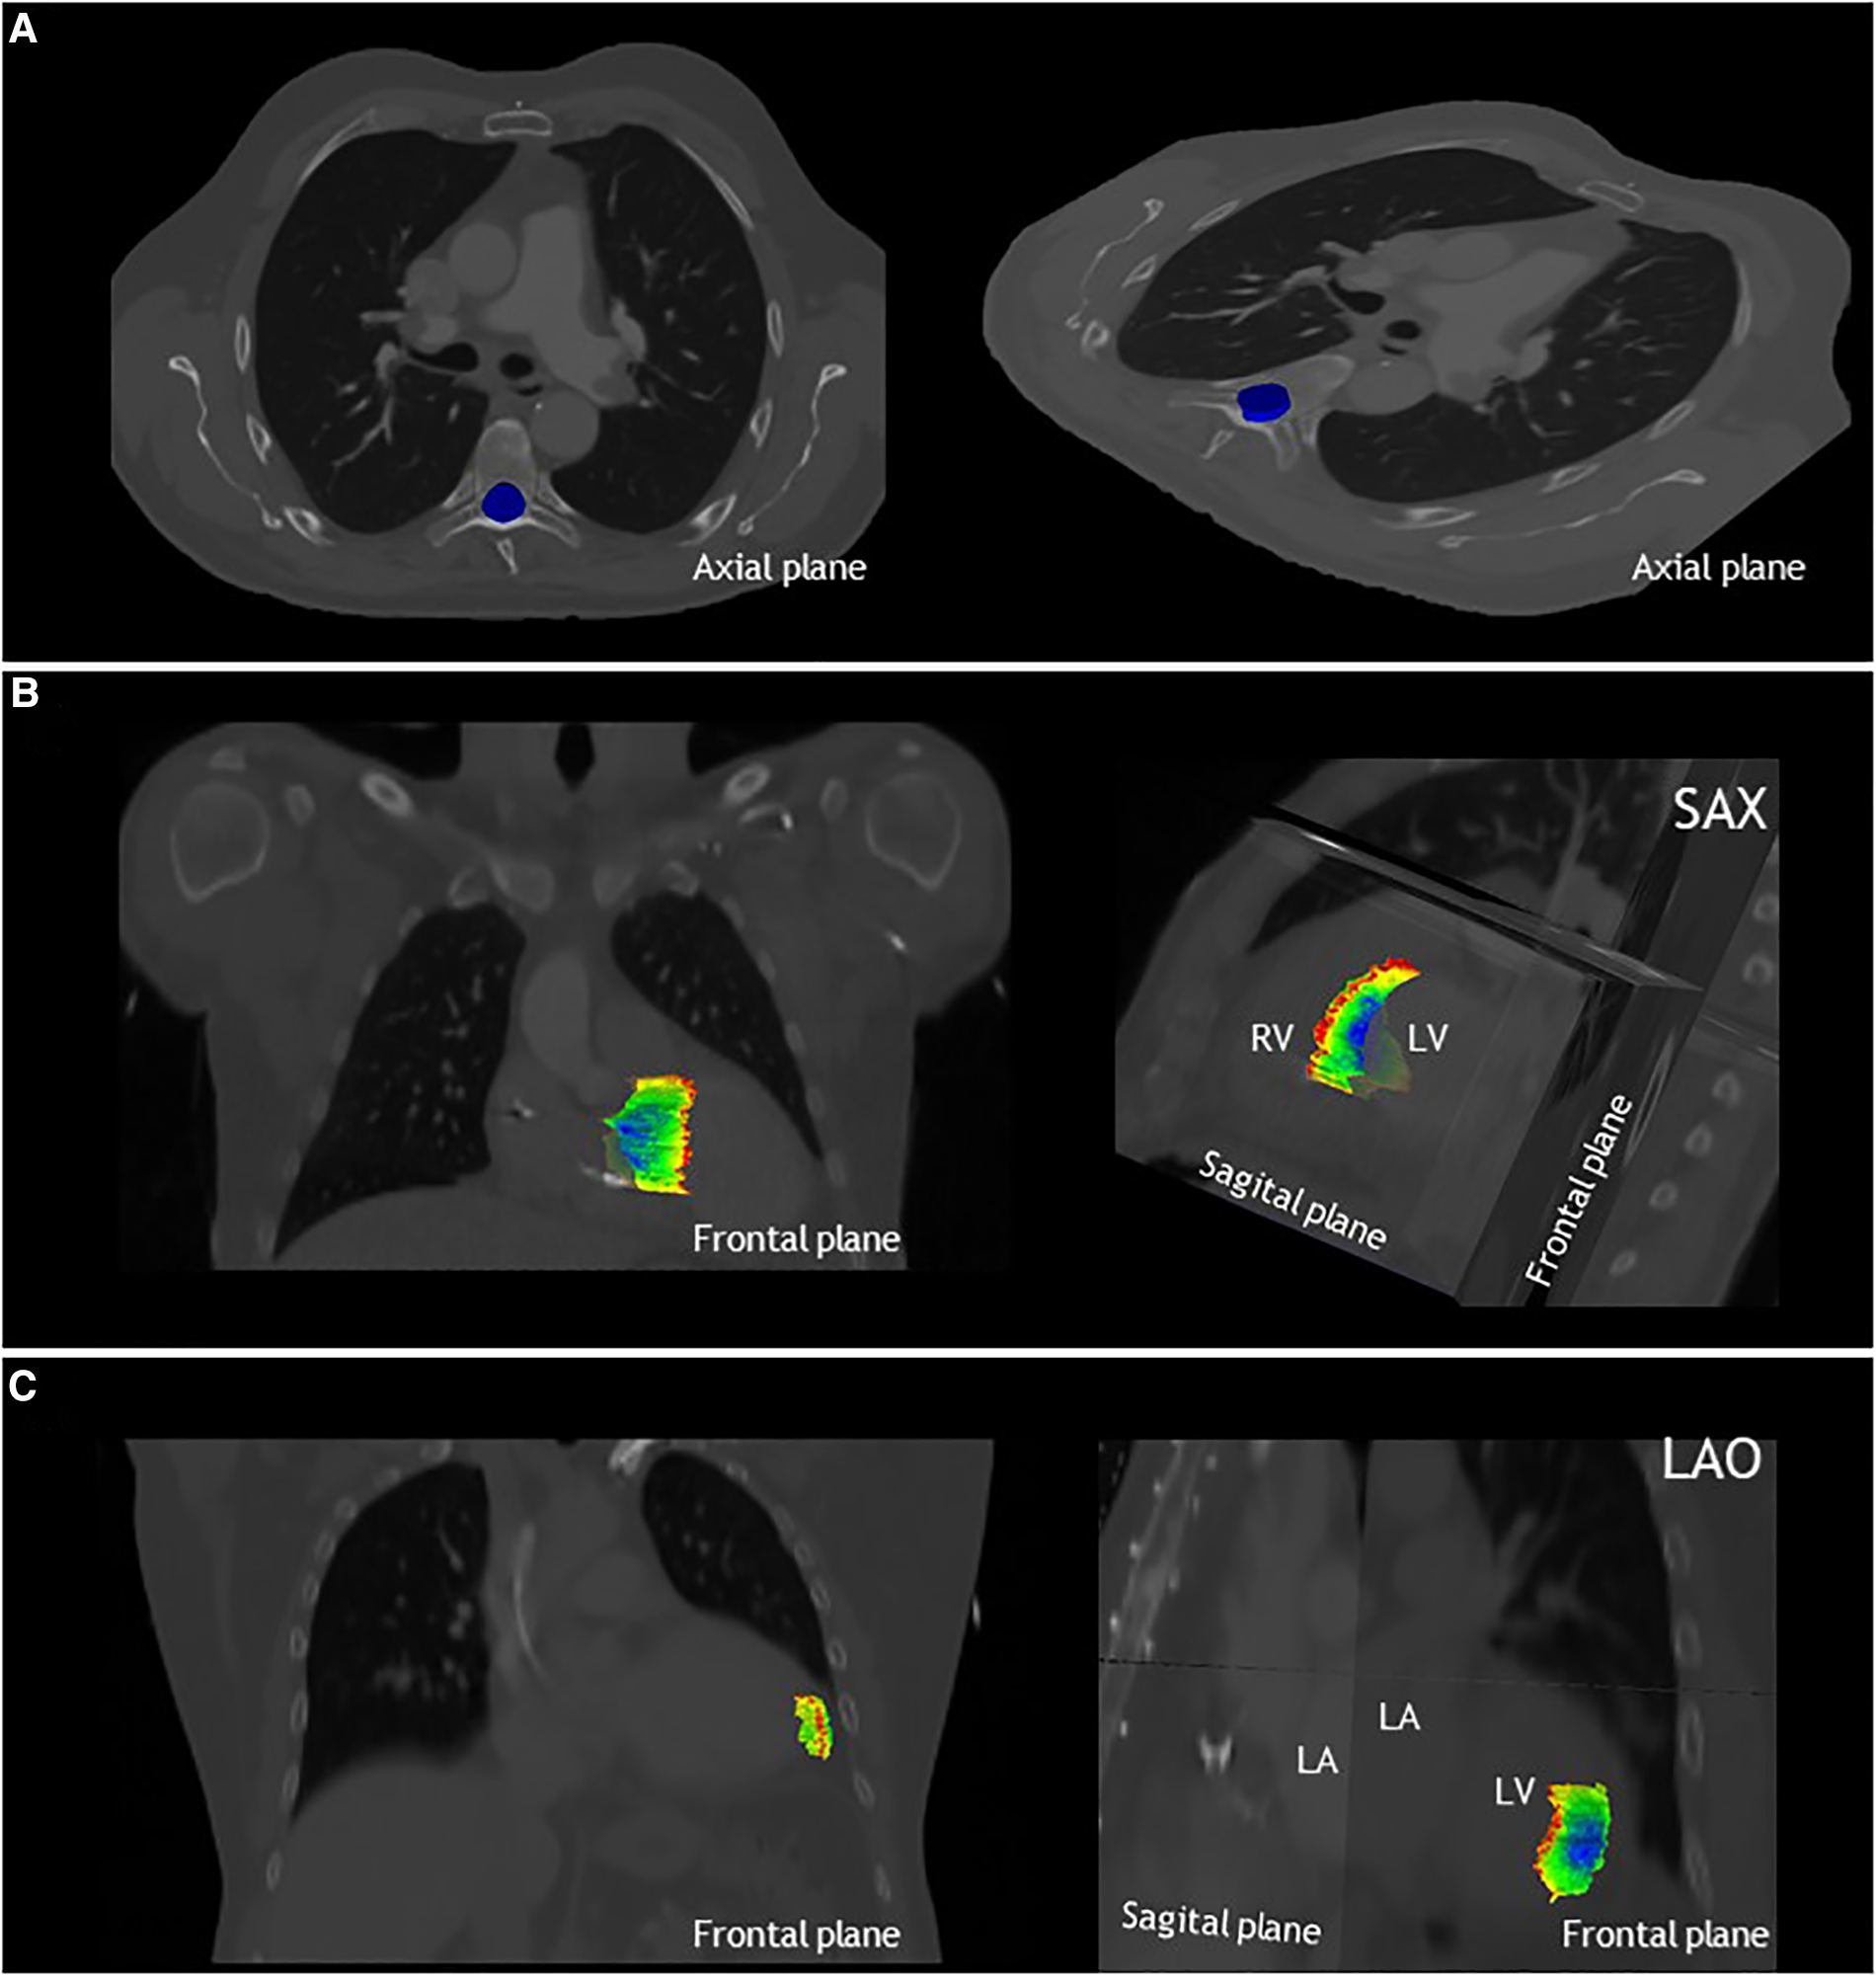

Figure 4

The local standard deviation projected on the median structure of the delineations, from dark blue: SD < 0.1 cm to red SD > 1.5 cm. (A) Results for phase 1, delineation of the spinal canal, projected on the axial plane for patient A. Note that the standard deviation is below <0.1 cm for the entire spinal canal. (B) Results for phase 2 of patient 2, delineation of the VT-target, projected on the frontal and sagittal planes. (C) Results for phase 3 of patient 3, delineation of the apical-lateral segment, projected on the frontal and sagittal plane. LA, left atrium; LAO, left anterior oblique view; LV, left ventricle; RV, right ventricle and SAX, cardiac short-axis view.

Low interobserver variation was found for the first phase of the study, the delineation of the spinal canal. This is indicated by low variation in the volumes (Table 2), low variation in distance to the median volume (RMS SD range 0.02–0.02 cm), and very high Dice coefficients (mean: 0.97 ± 0.01) (Table 2, Figures 3A, 4A).

Delineation of the VT-target based on case descriptions without advanced techniques resulted in high interobserver variability (Table 2, Figures 3B, 4B). The mean target volume ranged from 23–35 cm3 and widely differed per observer (range: 9.9–61.4 cm3, Table 2), as did the variation in distance to the median volume (RMS SD range: 0.5–1.02 cm, Table 2). The mean Dice coefficient for all three patients was 0.40 ± 0.15 with a range of 0.32–0.47 indicating low volume overlap.

Phase 3: segments

For phase 3, delineations of segments from the 17-segmented model showed equally high interobserver variation as phase 2 (Table 2, Figures 3C, 4C) as indicated by differences in delineated volumes between observers (Table 2), large variation in distance to the median volume (RMS SD range: 0.51–1.55 cm) and Dice coefficients below 0.5 (mean: 0.31 ± 0.21).